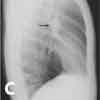

Inspiratory (A), expiratory (B), and lateral (C) chest radiographs confirmed the diagnosis of an endobronchial foreign body. Bronchoscopy revealed a blue pushpin obstructing the right bronchus intermedius and facing proximally into the large airways (D). The larynx, trachea, carina, and left main bronchus were not affected.

Chest radiographs may demonstrate air trapping, atelectasis, or consolidation and are suggestive of a radiopaque foreign body.4 In older children like this patient, chest radiographs should be obtained during inspiration and expiration. Fluoroscopy may be needed in young children. In a 10-year retrospective study, plain chest radiographs revealed a foreign body in only 23.56% of patients.5 In another retrospective study, chest radiographs were normal in 56% of children with tracheal foreign bodies.6